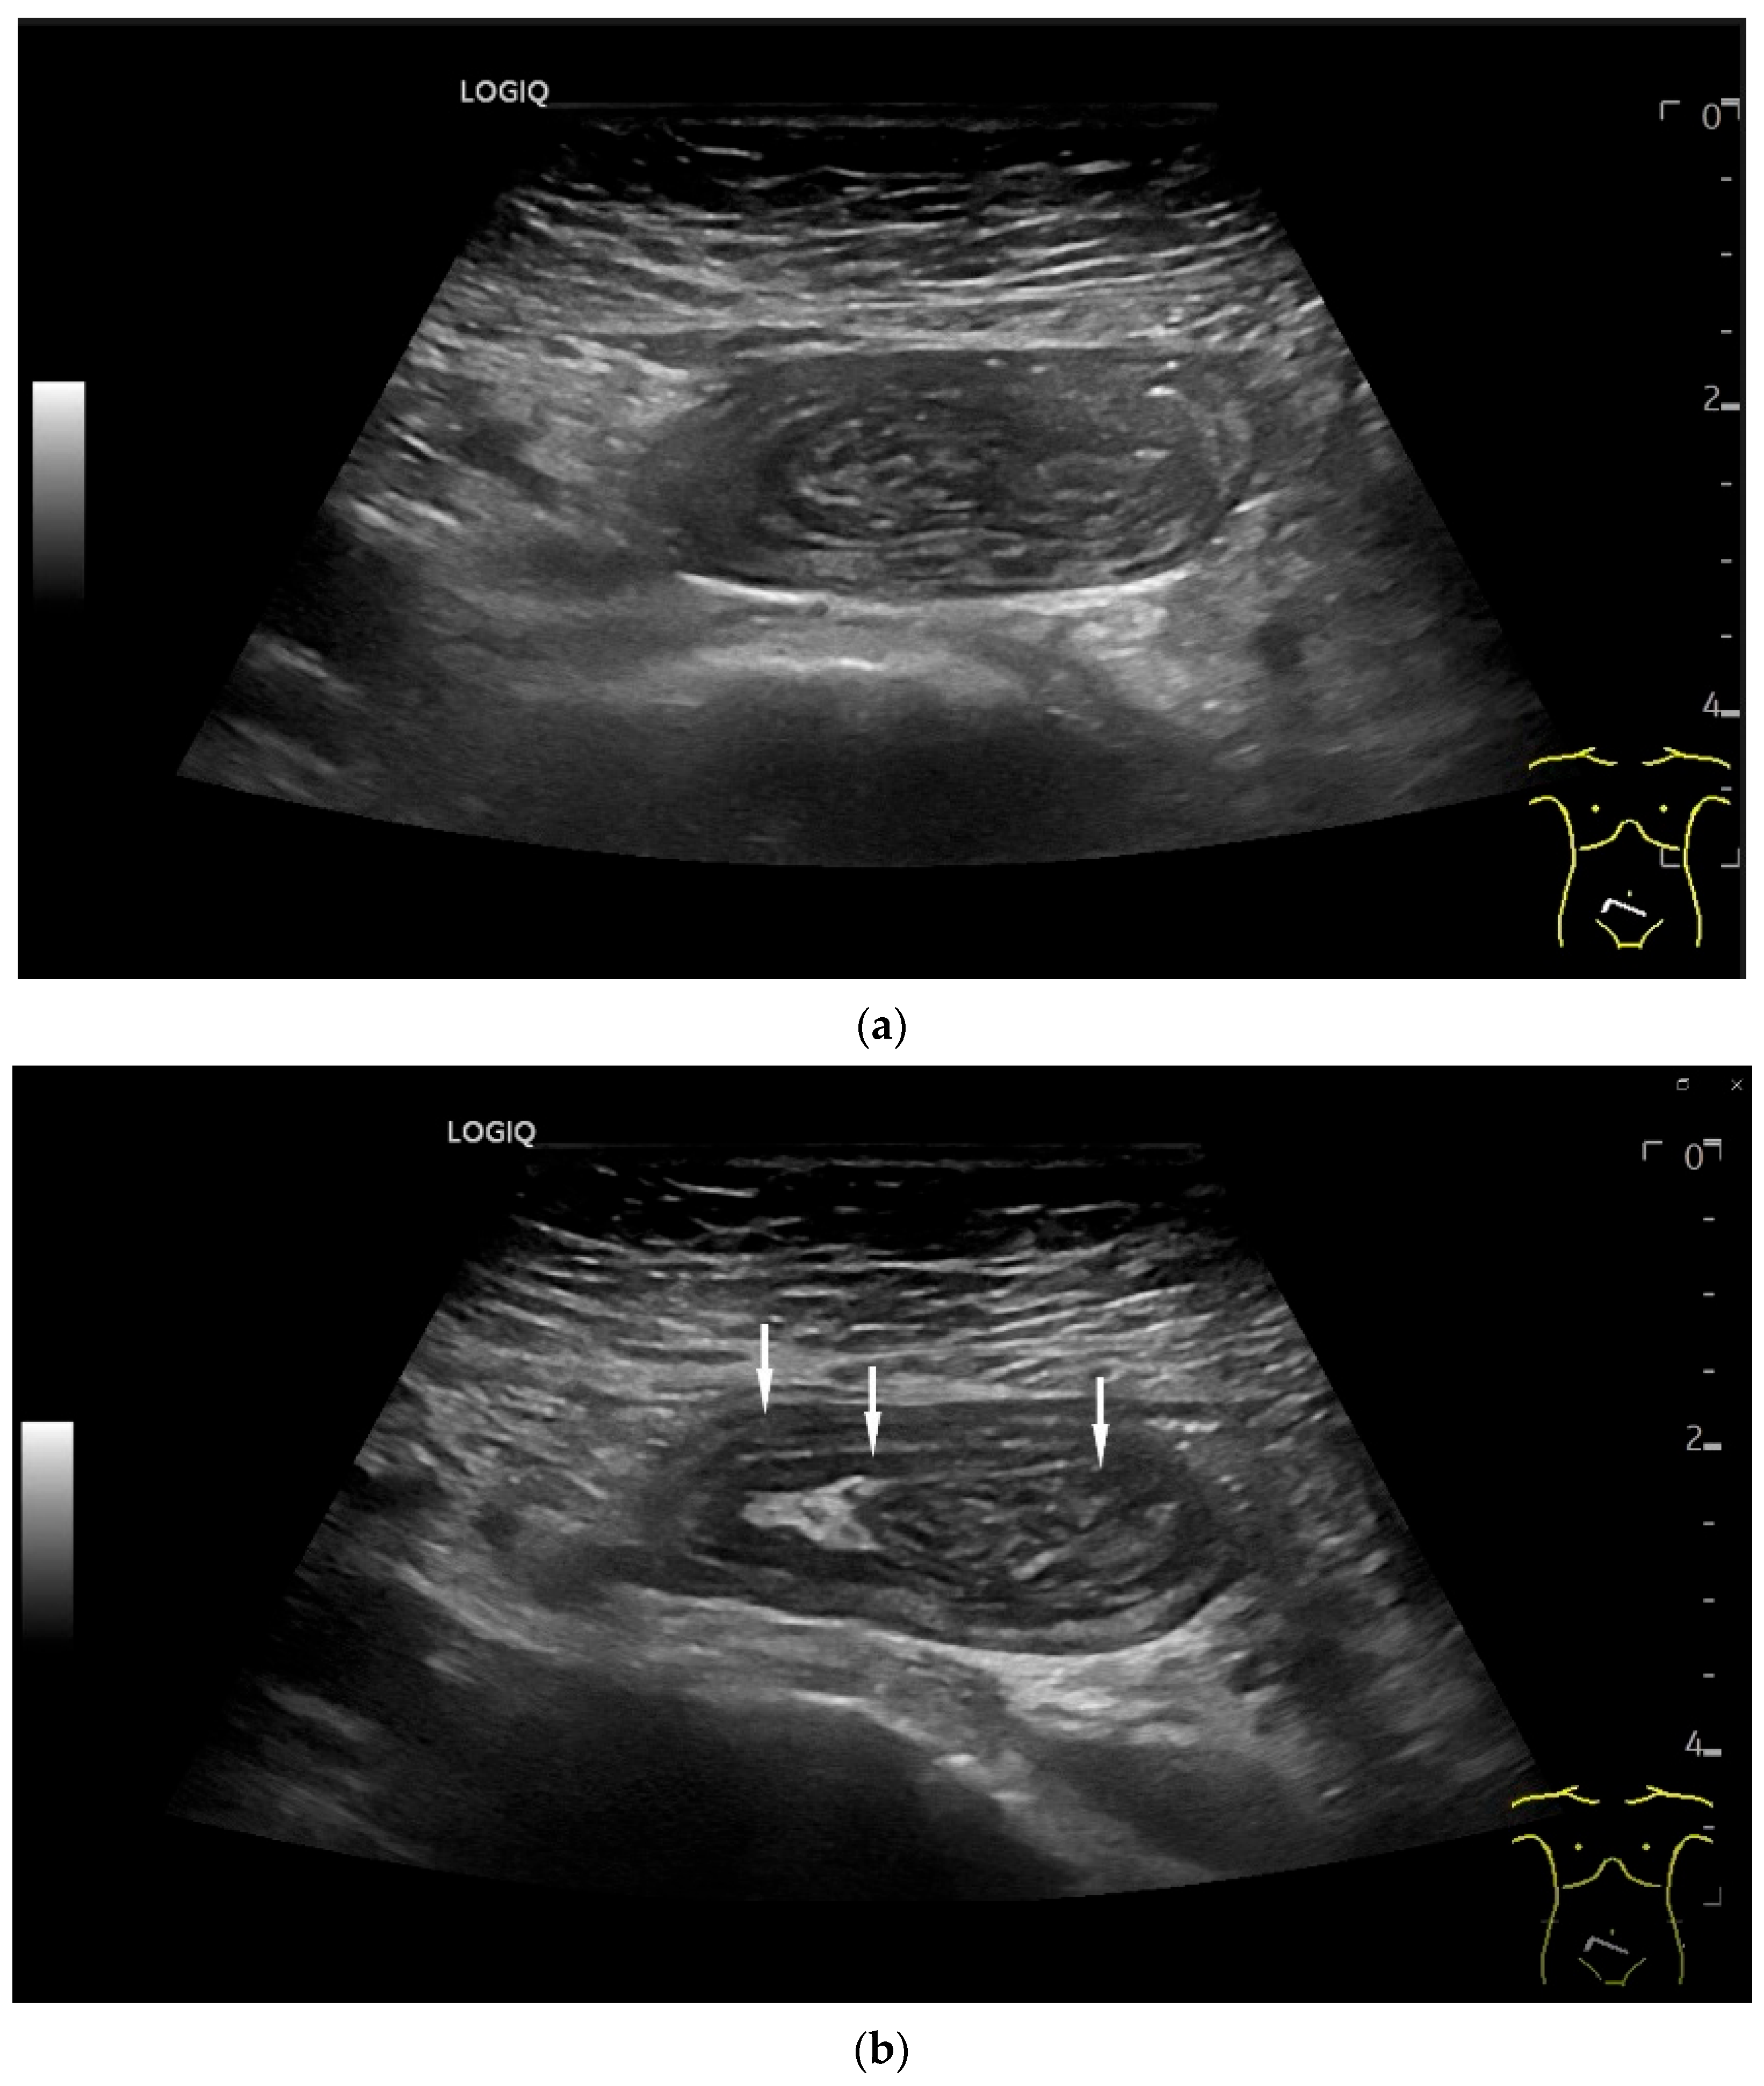

- Hasegawa, T.; Sumimura, J.; Mizutani, S.; Tazuke, Y.; Okuda, S.; Dezawa, T. The doughnut sign: An ultrasound finding in pediatric intestinal Burkitt’s lymphoma. Pediatr. Surg. Int. 1998, 13, 297–298. [Google Scholar] [CrossRef] [PubMed]

| Intussusception | The small intestine proximal to the tumor is invaginated. More than five wall layers are seen in an onion-skin shape. |